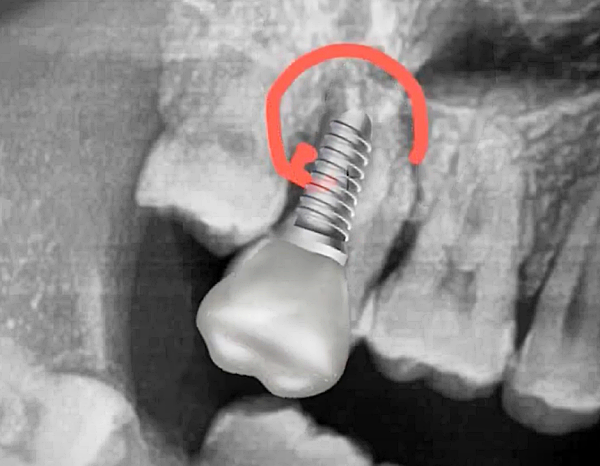

치아 뿌리 끝에 염증은 잇몸뼈를 녹이고 결국 치아를 흔들리게 만듭니다. 심한 경우 발치 후 임플란트 수술까지 고려해야 할 수도 있습니다. 따라서 재신경치료는 단순히 통증을 없애는 것이 아니라 자연치아를 보존하기 위한 중요한 치료입니다.

재신경치료 이후의 또 추가 치료 시, 치근단 절제술, 발치 후 임플란트 등의 치료를 고려해야 한다고 하니 참고하시기 바랍니다.